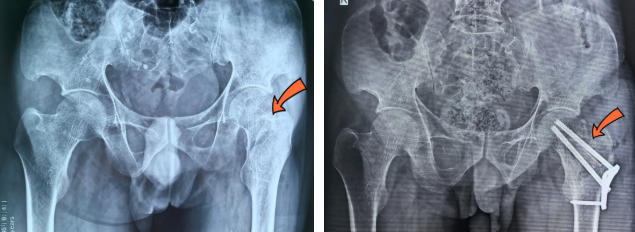

术前/术后

患者男性,39岁,因意外摔伤导致左髋部疼痛难忍,急入我院就诊,X线片检查显示:左侧股骨颈骨科,收治于骨科。患者既往有肾移植术后4年,合并高血压3级(极高危),腔隙性脑梗,且长期服用排异药物、激素等,用药种类多、病情复杂,手术风险较大。

对此,医务科积极组织骨科、肾内科、手麻科等开展多学科会诊,充分评估病情,排除手术禁忌症后,最终确定实施股骨颈骨折切开复位内固定+带血管蒂腓骨移植术。前者可实现骨折断端精准对位固定,后者通过移植带血供的腓骨,为骨折区域提供充足血运。因患者是股骨颈头下型骨折,股骨头坏死率高,进行腓骨移植能给股骨头重建血供,减少坏死率,减轻患者痛苦。